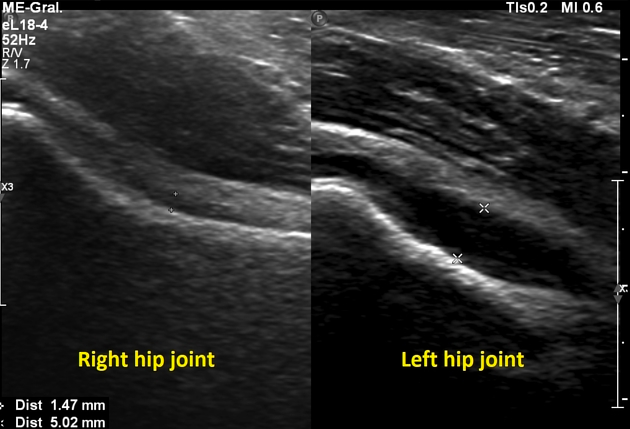

Diagnostic Ultrasound

Diagnostic Ultrasound is a very useful assessment tool to visualise the outer edge of the hip joint and see any inflammation associated with FIA.

Ultrasound has the additional benefit of being able to assess the joint during movement, as it does not have to be done in a static position. This gives real time information about how the joint and soft tissues of the hip are affected during movement. Where appropriate, ultrasound can also be used to guide an injection into the hip joint to help with the pain associated with FAI.

At Complete we are able to offer a unique service, as many physiotherapists are also highly experienced sonographers, who are able to carry out a diagnostic ultrasound of your hip at your initial appointment.

The image on the left shows the front of a normal hip joint on ultrasound. The image on the right shows fluid (the black space between the two cursors) indicating a significant joint swelling and inflammation. It is not uncommon that this will require an ultrasound guided corticosteroid injection to help the pain.